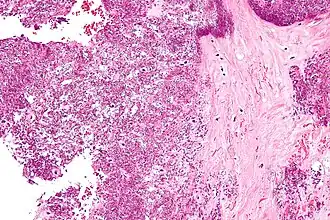

Microfotografia mostrando a deposição de cristais em um disco intervertebral. Coloração H&E.

Cristais de Deposição De Pirofosfato De Cálcio Diidratado tendem a formar dentro de tecidos articulares. O diagnóstico é feito por microscópio, com a análise do fluido de uma junta. Radiografias da junta podem mostrar sinais de Condrocalcinose. Depósitos Assintomáticos podem se formar na cartilagem, articulações, discos intervertebrais, tendões e ligamentos. A deposição de cristais dentro da cartilagem (hialina e fibrocartilagem) é conhecido como condrocalcinose. É inicialmente só visível no microscópio, mas se houver bastante calcificação, pode ser visto com a ajuda da radiografia também. Locais comuns de condrocalcinose incluem os joelhos, punhos, cotovelos, e quadris.